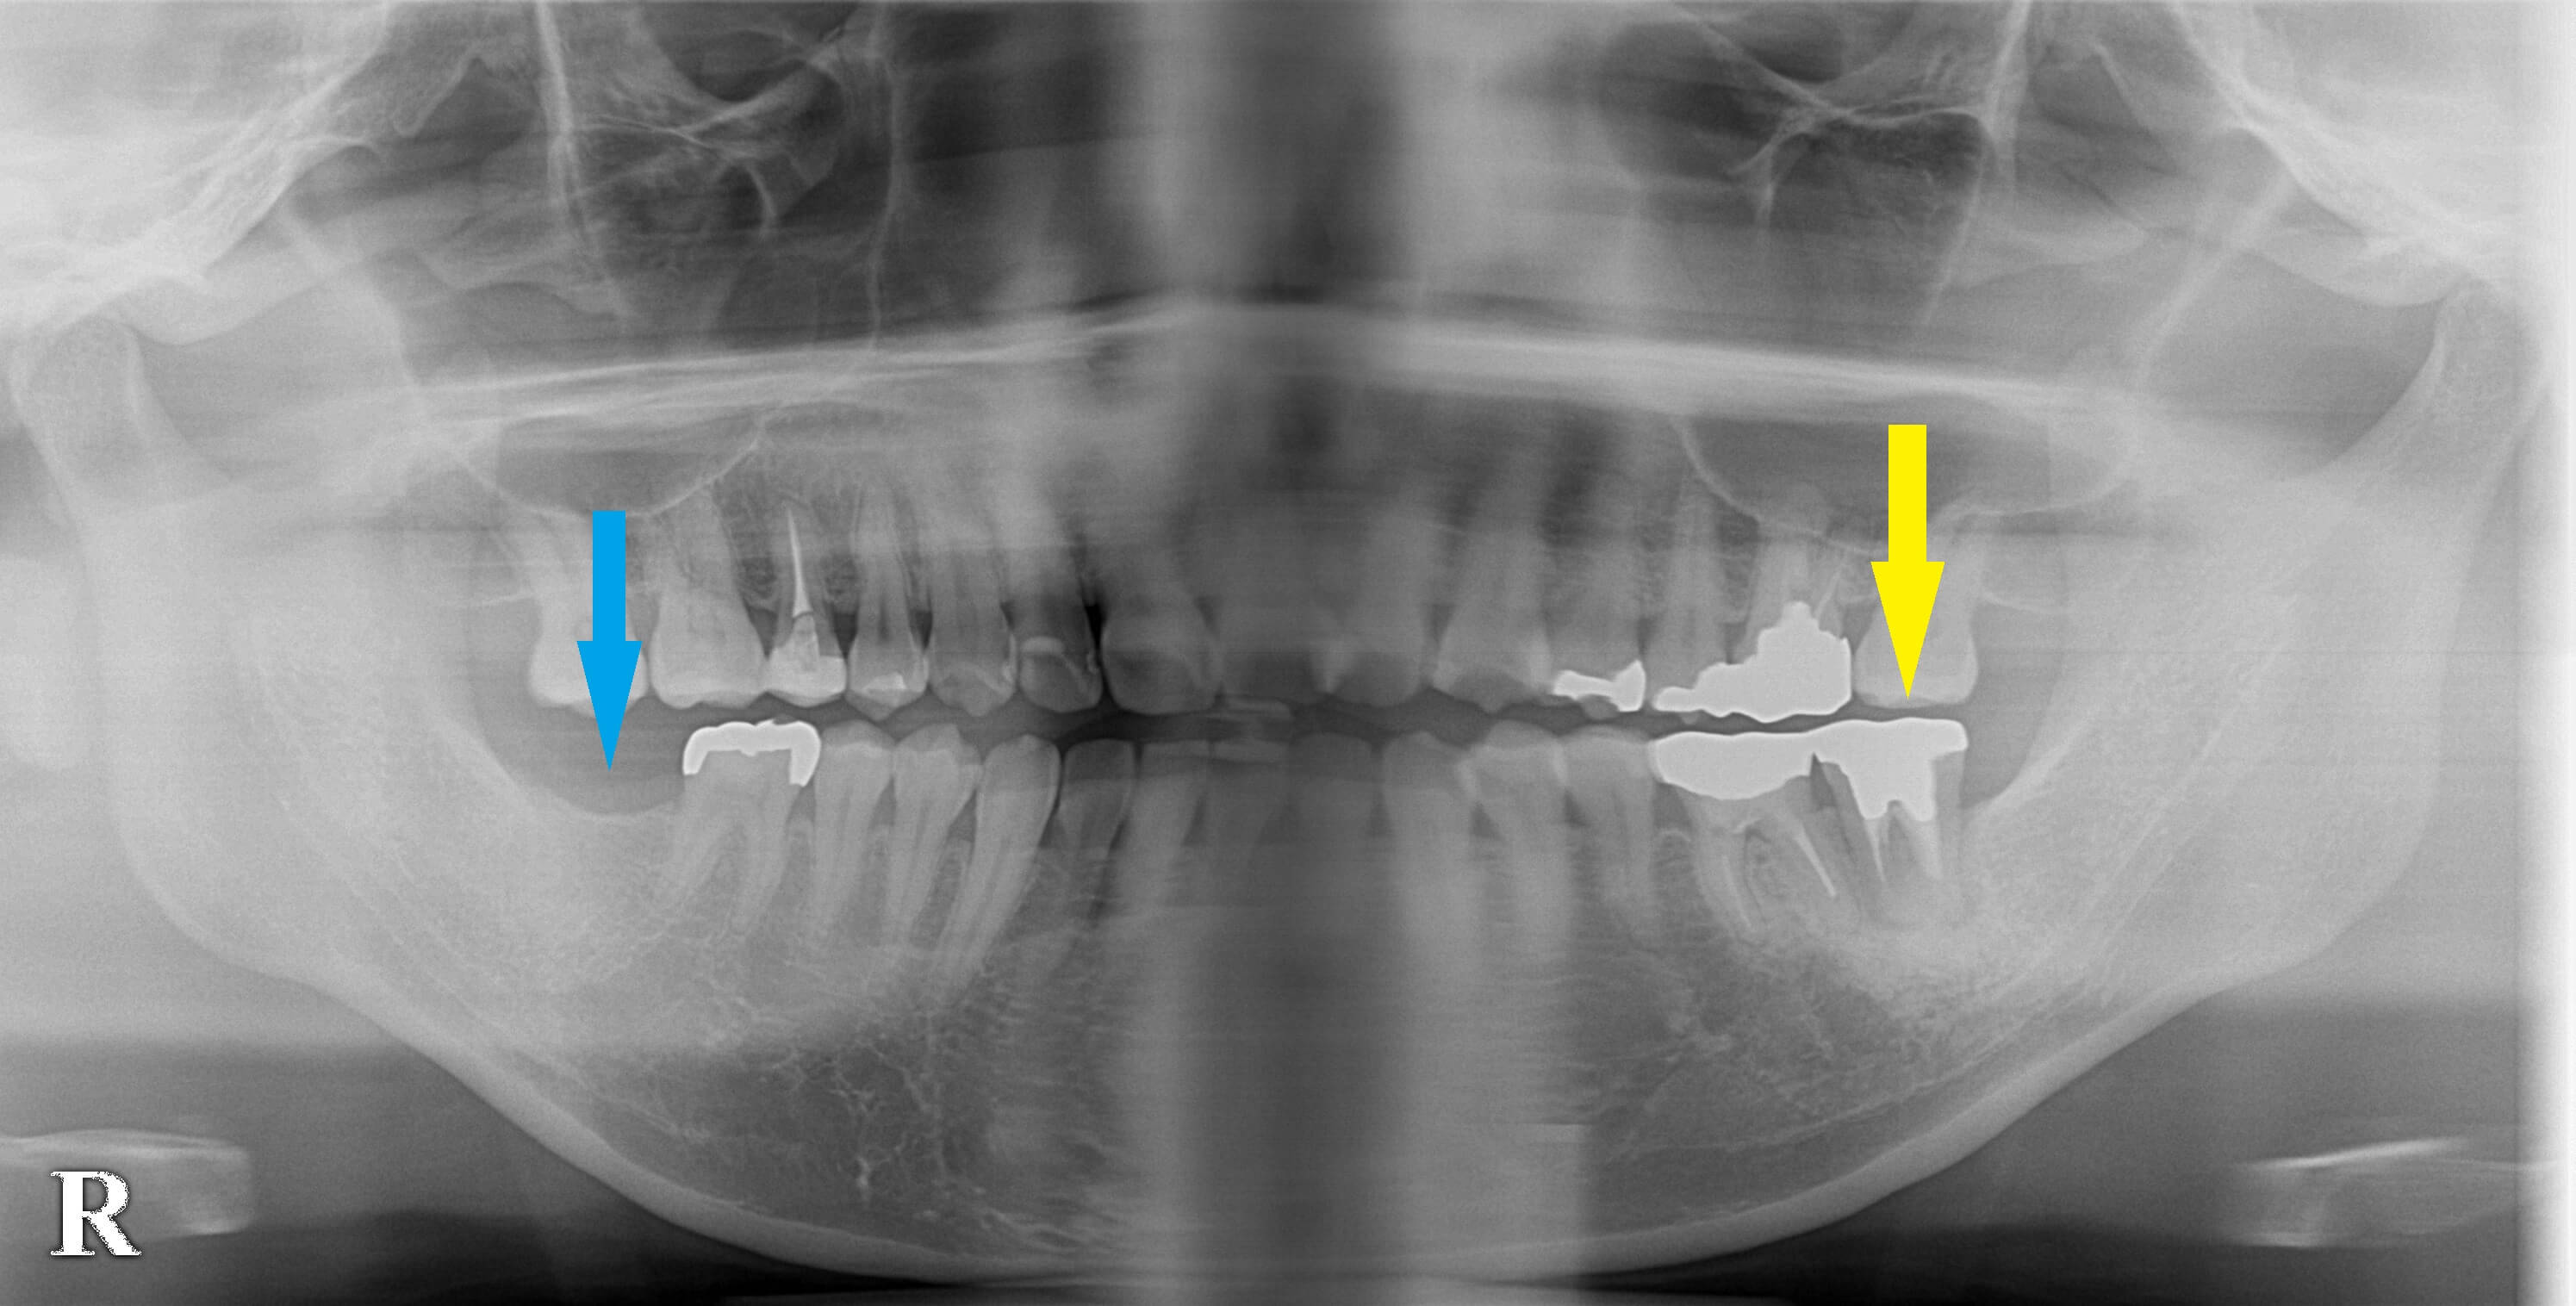

数か月前に右下顎第二大臼歯の欠損(写真青矢印)で、インプラント治療を希望されて来院され、1本インプラント埋入を行って上部構造を装着し治療が終了していた患者様です。

来院当初から、左下顎の第二大臼歯も歯根破折が疑われ、症状がひどくなったら、抜歯してインプラントが必要と説明をさせていただいていました(写真黄矢印)。